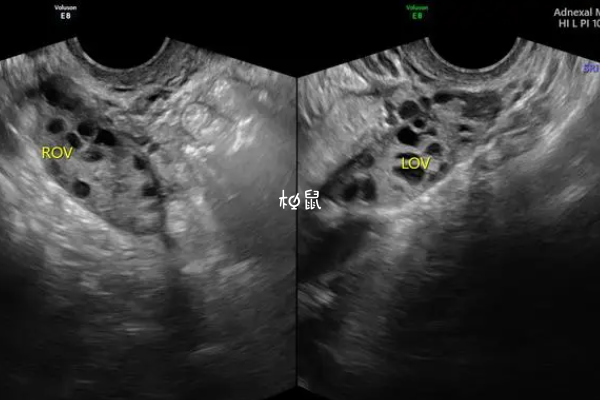

如果患有多囊卵巢综合征等内分泌失调的疾病,则可能会影响卵泡的正常发育,若卵泡不能发育为成熟的优势卵泡,需要定期进行超声检查。另外,当卵泡直径达到25x25mm时,然后没有破裂便形成了卵泡黄素化,是无排卵型月经的一种特殊类型,在临床上可以引起不孕不育。